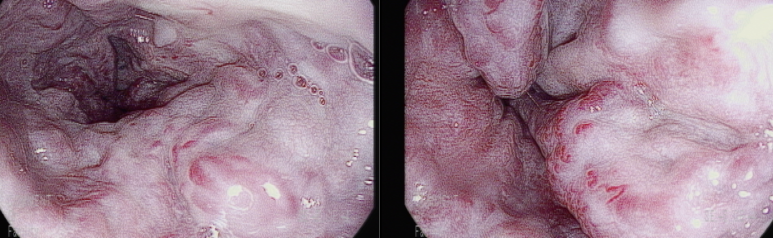

2년전 검진 위내시경; LsF3CbRCS(+++) 소견의 식도정맥류, 이전에 결찰술(EVL) 자국이 관찰되나

하부식도에 whale sign등 위험 소견을 동반한 모습

대학병원 재직시 복수의 밴드(multiband)를 이용하여 2-3 줄의 식도 정맥류를 동시에 결찰하거나 하였다. 시술 중 출혈하기도 하고 심히 집중해야 하는 시술중에 하나이다.